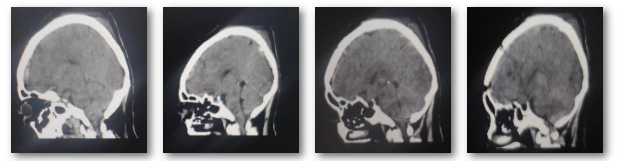

入院后,为更准确诊断病情和制定最佳治疗方案,神经外科二病区主任白西民及团队根据影像学资料、病史、查体分析诊断:左额部窦镰旁及鞍结节多发占位,较大者大小约6.0*5.3*5.7cm,与周围神经血管粘连紧密,考虑为脑膜瘤可能,且肿瘤巨大,需尽快手术治疗。经过多次研讨,与家属充分沟通,科室为吴女士制定详细周密手术方案。

术中,经过初步探查发现,手术比想象得更难,医生面临的考验,不仅要切除肿瘤,还要尽可能保护血管及神经功能。白西民带领团队在手术显微镜下沉着应对,先切断肿瘤的血液供应控制出血,分块切除肿瘤,凭借精湛手术技巧和丰富临床经验对肿瘤进行精细剥离,仔细保护与肿瘤粘连紧密的重要神经、血管结构。

手术从上午08:40一直持续到晚上20:05分,经过近12个小时的“刀尖惊魂”,凭借精湛手术技巧和丰富临床经验,不仅顺利将肿瘤完整剥离,而且完整保留了神经功能,手术取得圆满成功。